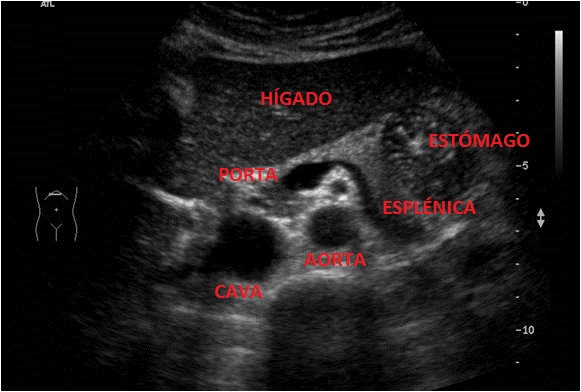

El Páncreas se encuentra rodeado de la siguiente anatomía:

Como ves el Páncreas se encuentra situado en una región anatómica donde un montón de estructuras se concentran en muy poco espacio lo que compromete la visualización y hace que sea uno de los órganos más complicados de estudiar dentro del protocolo de Abdomen.

Se encuentra situado según la imagen anterior, posterior al Hígado y anterior a la aorta, pero lo que de verdad nos sirve de referencia para encontrar el órgano es una imagen en forma de renacuajo, anecoica y que en la imagen siguiente está silueteada en blanco.

Esta es la referencia más importante para encontrar el páncreas cuando lo estudiemos, encontrar esta estructura anecoica, que pasa justo posterior al órgano que lo acompaña y lo marca, que tiene forma de renacuajo y que es la Esplénica en su parte más delgada y la Porta en su parte más gruesa. Es sin duda la estructura que va a ayudarte, la aliada principal para encontrar ecográficamente el Páncreas.